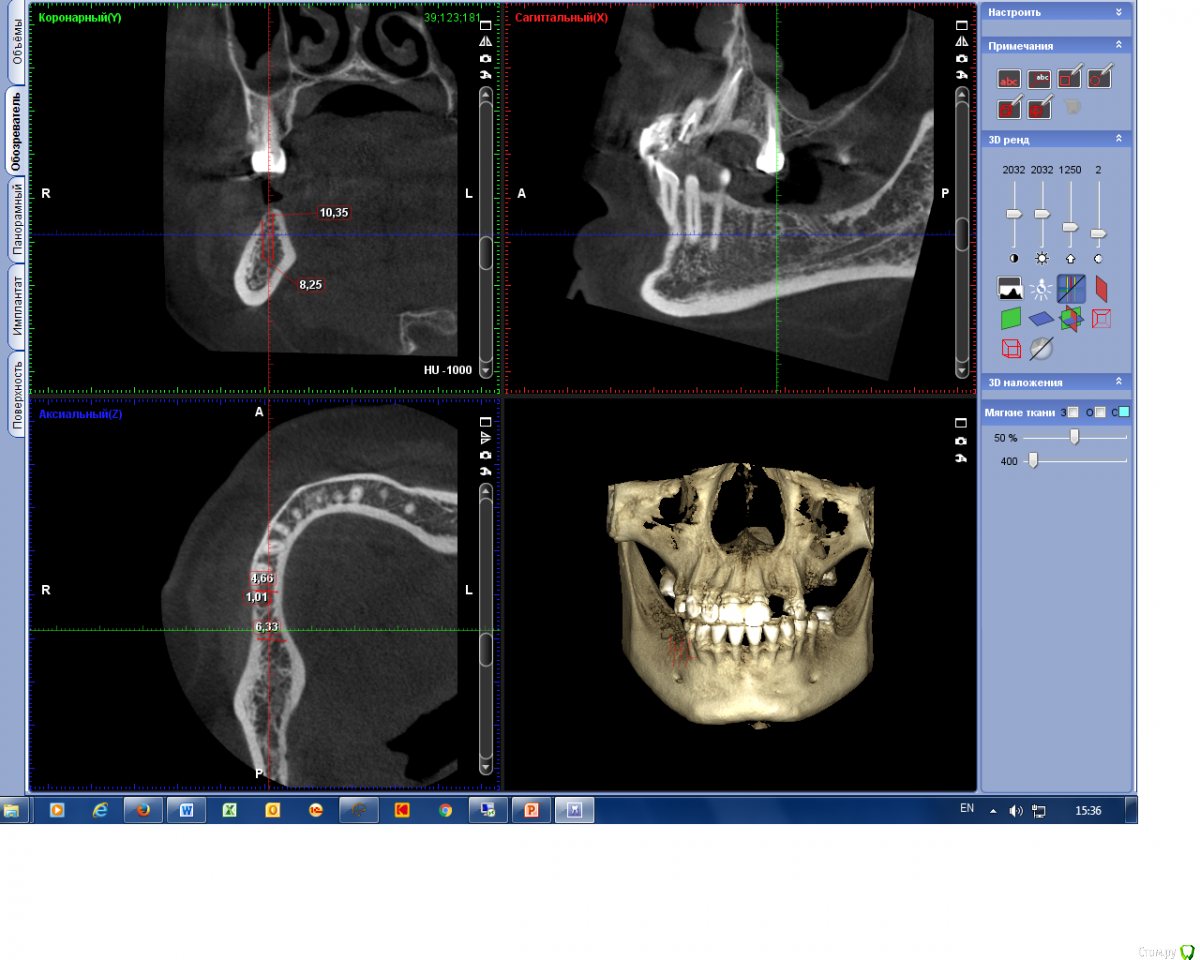

togrul Опубликовано 4 апреля, 2016 Поделиться Опубликовано 4 апреля, 2016 (изменено) Добрый день коллеги. Подскажите пожалуйста какую методикукостной пластики выбрать в области премоляра? Расщепление? Изменено 4 апреля, 2016 пользователем togrul Ссылка на комментарий

alekszander Опубликовано 5 апреля, 2016 Поделиться Опубликовано 5 апреля, 2016 срезы на середине гребня, там некуда ставить даже 3.6 без пластики. Про расщепление не скажу - не пробовал ни разу. В подобном случае сделал так: поставил импланты 3.6 забор ауто во время сверления+с дистального участка ауто, сверху миксApatos+ауто и мембраной с пинами(сосидж). Хотя да - расщепление было бы дешевле. Ссылка на комментарий